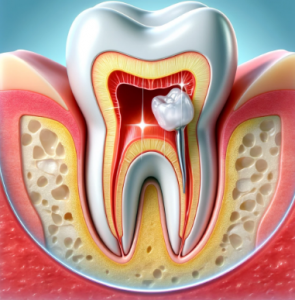

충치 치료의 종류에 대해 알아보기전에 치아의 구성 조직들에 대해 이해하는 것이 필요합니다. 어려울 것 없는데요. 그 구성 조직들이 충치에 감염되는 범위에 따라 충치 종류가 나눠진다고 보시면 되겠습니다. 아래는 치아의 구성 요소입니다.

- 에나멜

- 상아질

- 치수

- 치근

여기서 에나멜은 흔히 말해 겉으로 보이는 가장 바깥쪽의 매우 단단한 하얀색 치아를 말합니다. 그냥 거울을 통해 보았을 때, 육안으로 바로 보이는 것이 에나멜이라고 보시면 되겠습니다. 에나멜이 감염되면 그냥 깍아서 레진 충전을 통해 치료만 하면 됩니다. 가장 경미한 단계이죠.

그 다음 상아질은 에나멜의 내부라고 보시면 되는데요. 미네랄 함량이 적기 때문에 에나멜보다는 부드러운 조직에 속하며 이 때부터 중간 단계라 보시면 됩니다. 상아질에는 관이 있기 때문에 세균이 더욱 빠르게 확산되는데요. 그래서 겉으로 보이는 충치보다 실제 충치는 더욱 큰 범위로 확산되어있는 것이죠.

마지막으로는 치수 입니다. 치아 내부의 연조직으로써 신경과 혈관이 모여있는 곳을 말합니다. 즉 이 때부터는 신경치료의 범위에 해당 하게 됩니다. 이 때 두가지로 나눌 수 있는데요. 신경치료는 다행히 근관치료를 통해 자연치아를 보존할 수 있지만, 감염이 심할 경우 발치와 같은 침습치료가 필요할 수 있습니다.